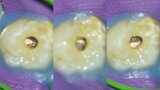

Autogenous transplantation followed by conservative root canal therapy: Three years follow-up